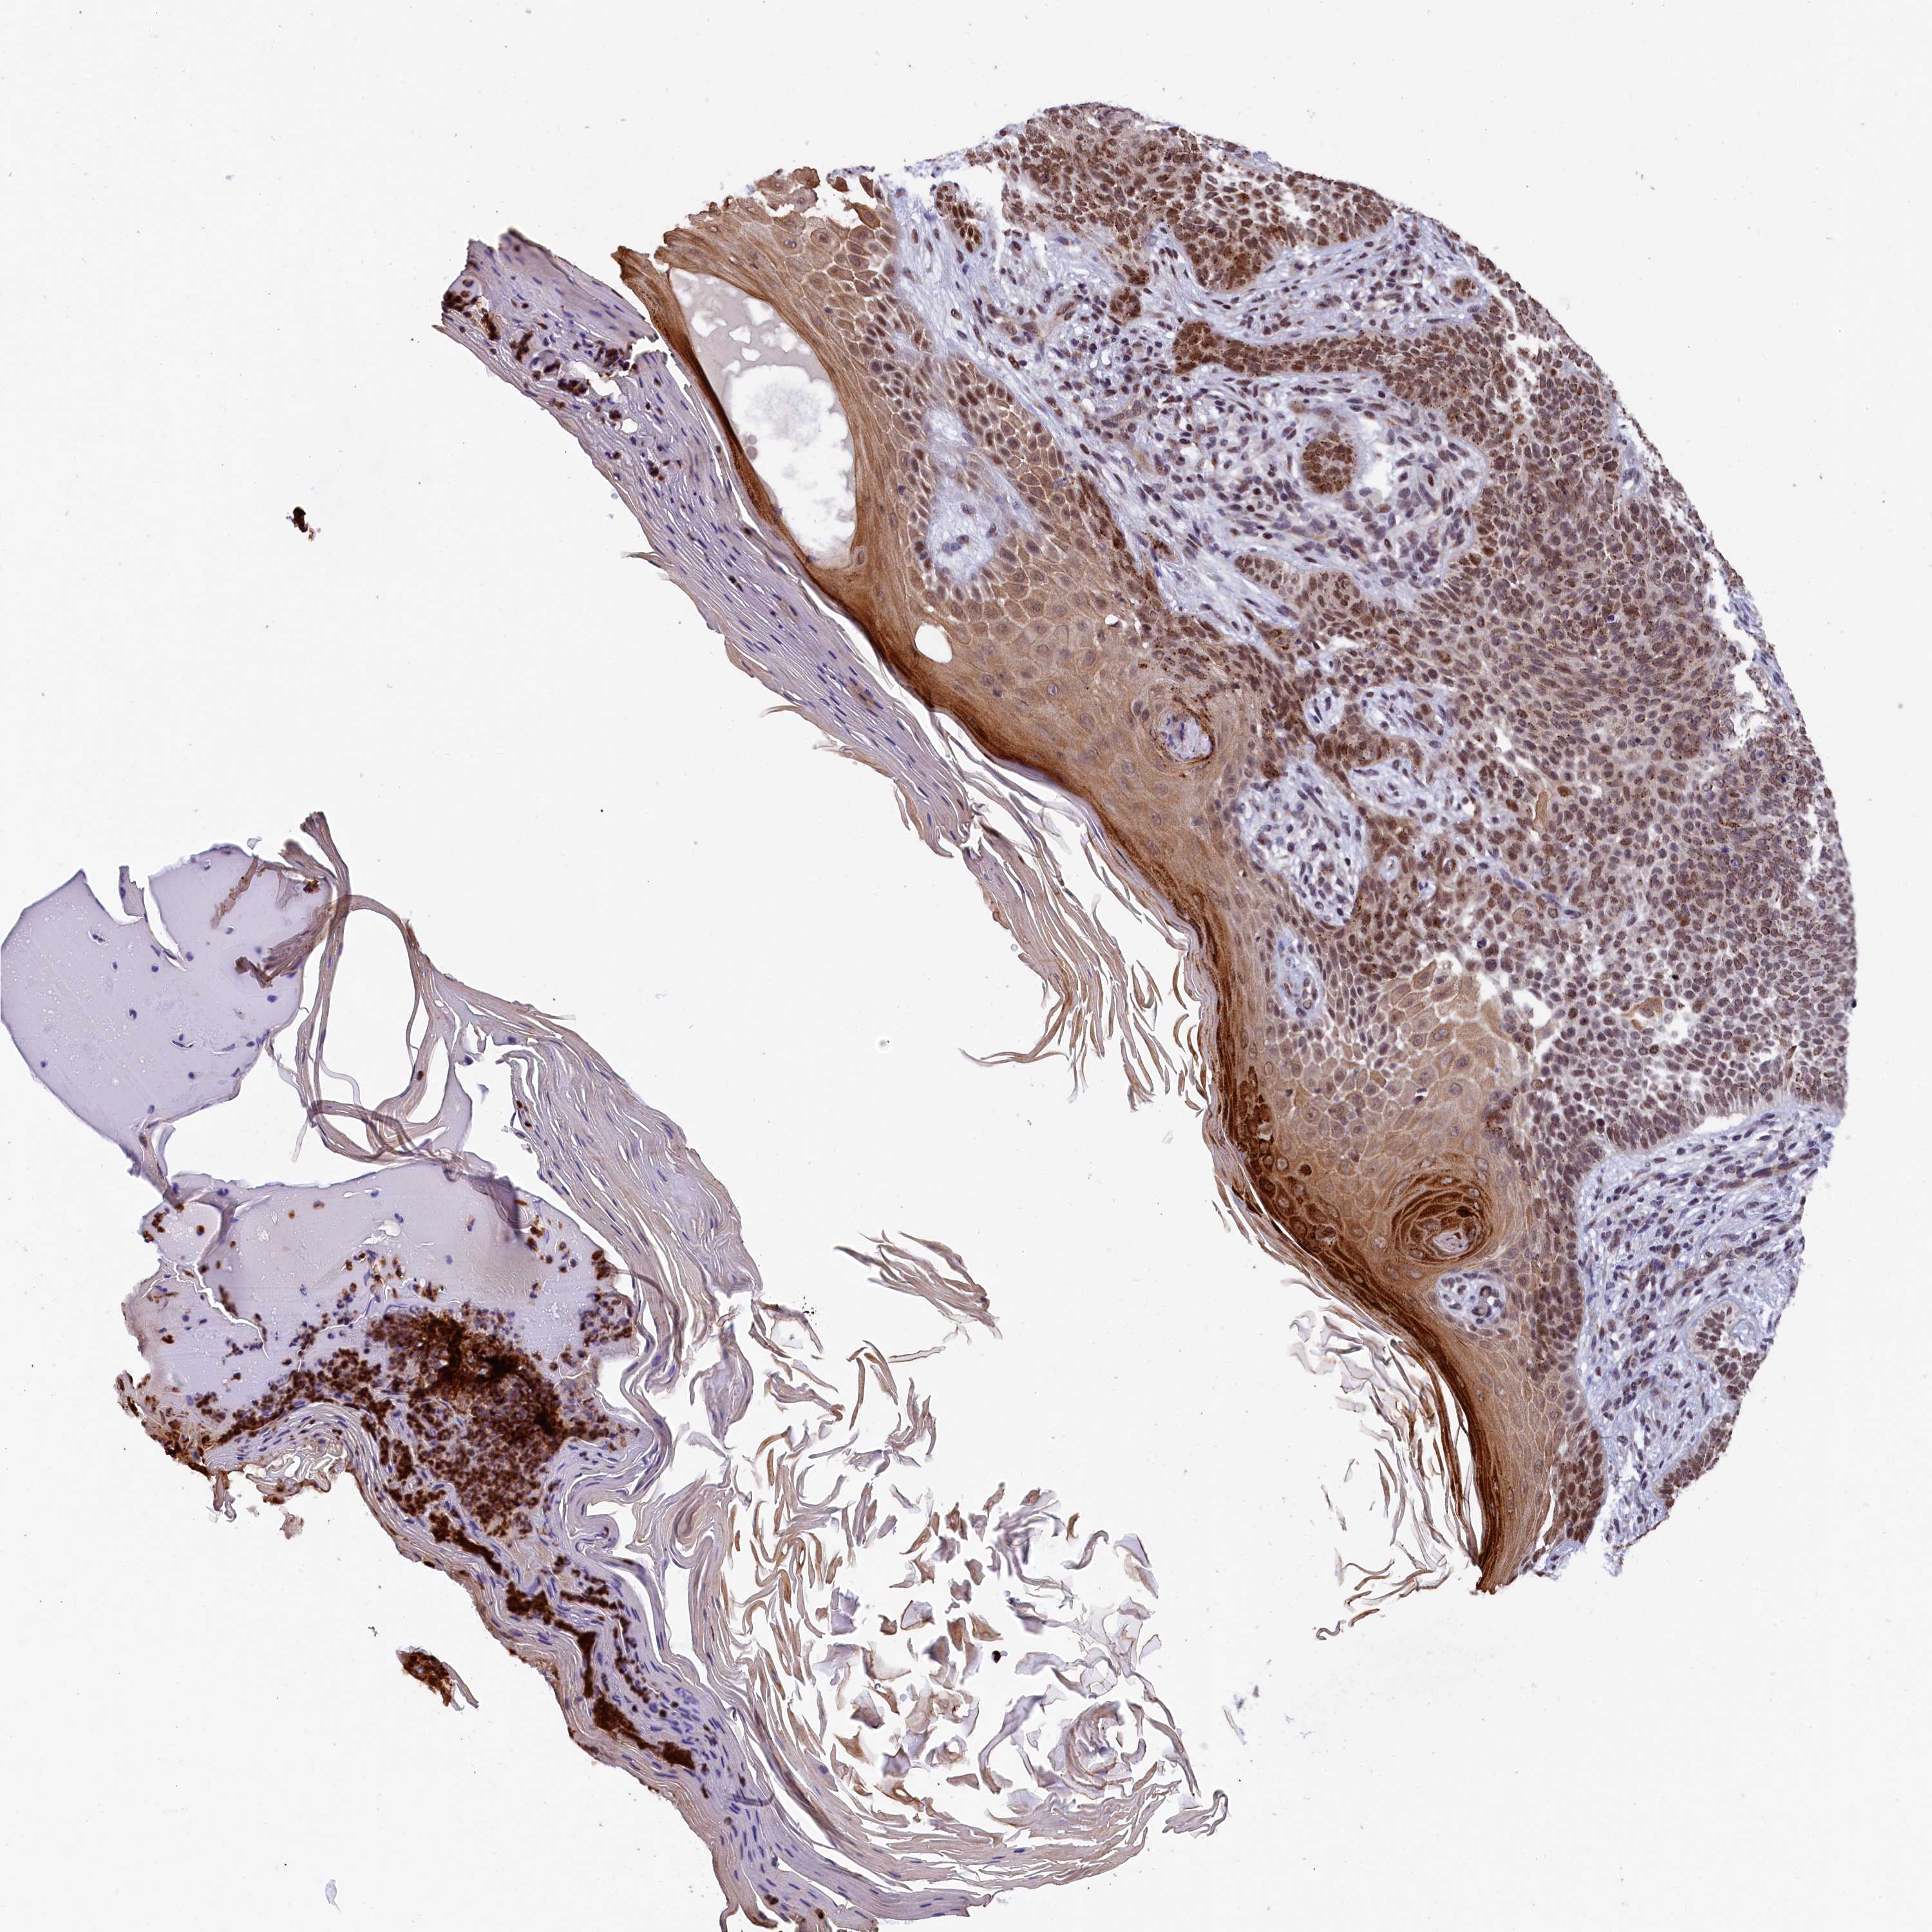

Basal cell and squamous cell cancer

SKIN CANCER - Protein expressioni

A mouse-over function shows sample information and annotation data. Click on an image to view it in a full screen mode. Samples can be filtered based on level of antibody staining by selecting one or several of the following categories: high, medium, low and not detected. The assay and annotation is described here.

Antibody stainingi

Antibody staining in the annotated cell types in the current human tissue is reported as not detected, low, medium, or high, based on conventional immunohistochemistry profiling in selected tissues. This score is based on the combination of the staining intensity and fraction of stained cells.

Each image is clickable and will lead to virtual microscopy that enables deeper exploration of all samples and also displays staining intensity scores, fraction scores and subcellular localization as well as patient and tissue information for each sample.

Antibody HPA041124

Staining

High

Strong

Quantity

Location

Basal cell carcinoma